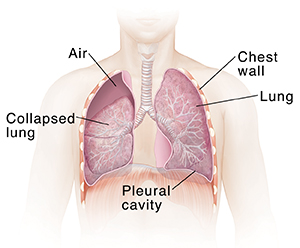

A collapsed lung (pneumothorax)

If part of the lung wall breaks or ruptures, air may leak into the pleural cavity. This is the space between the lungs and the chest wall. A pneumothorax is when air collects in this space. It can lead to lung collapse. There are several types of pneumothorax with different causes. Pneumothorax can be caused by diseases such as pneumonia or COPD (chronic obstructive pulmonary disease), trauma or injury to the chest, or activities with dramatic changes of air pressure such as flying or deep sea diving. Tubes placed with surgery can drain air from the pleural cavity so the lung re-expands. During surgery, the wall of the lung can also be fixed so it's less likely to collapse again.

| Removing air allows a collapsed lung to expand. |